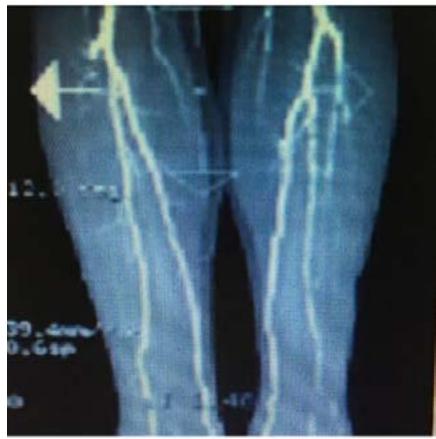

Fig.14 arteria peroneal blocked

Case 12: The arteria peroneal of a 76-year-old man was blocked as shown in Fig. 14. Doctor suggested him to take an operation after the other two vascular being blocked. He asked us to help. We gave him 40 minutes MRT in the afternoon. At that night, as he was sleeping, he felt terrible itch on shank and foot. And he thought why there were so many mosquitoes this night. Suddenly, he understood that not mosquito but the blood was flowing though the shank and foot. Nevertheless, we gave him two days MRT again (40 minutes/day) and suggested him to take another test. He said: "no need, I can feel it is very well". Now he is 90 years old and can walk $500\mathrm{m}$ by push a wheelchair.